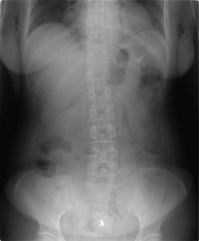

下の2枚のレントゲン写真はどちらも大腸内視鏡検査直後のものです。

通常の空気を入れて検査をした場合

黒く見えるのは大腸と小腸に入った空気です。お腹が空気でふくらんでいることがわかります。

二酸化炭素を入れて検査をした場合

大腸検査直後ですが、すでに大腸内の二酸化炭素はほぼ吸収され黒い部分がほとんどありません。